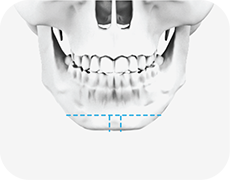

01

턱의 끝부분을 T자 모양으로 절골